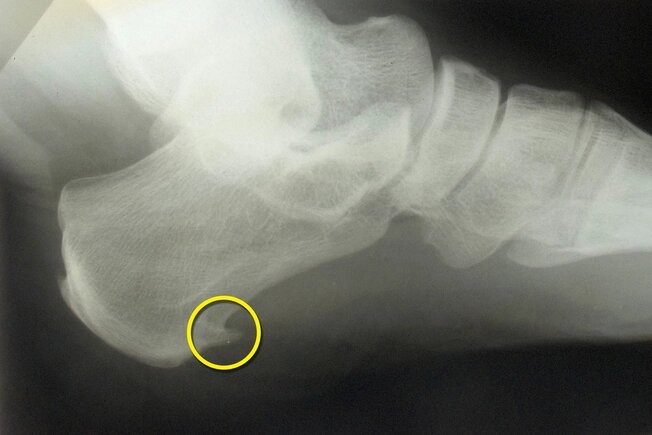

Pinteni ososi

Este posibil să confundați acești pinteni osoși cu bunioni. În cazul bunions, oasele sunt deplasate..Pinteni ososi, pe de altă parte, sunt excrescențe de pe marginile oaselor piciorului, adesea pe călcâi, mijlocul piciorului sau degetul mare. Dacă devin suficient de mari, vor exercita presiune asupra nervilor și țesutului din apropiere și vor provoca durere. Aceste excrescente pot fi cauzate de osteoartrita sau de o entorsa a tendonului sau ligamentului, care sunt mai frecvente pe masura ce inaintati in varsta, mai ales dupa varsta de 60 de ani.